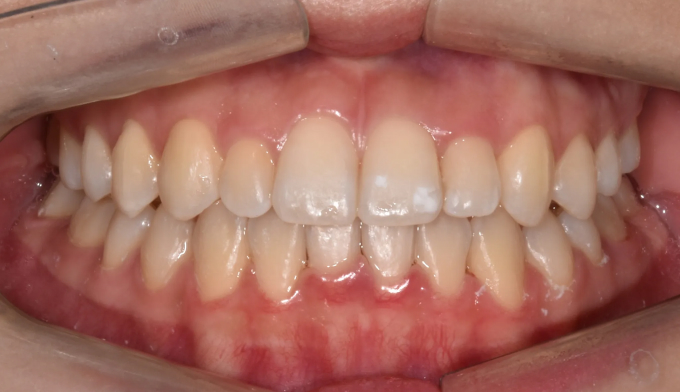

덧니

얇은 입술과 뒤로 들어간 입술을 가지고 있기 때문에 발치를 하지 않고 확장과 후방이동을 통해 최대한 공간을 마련하여 교정하기로 하였습니다.

덧니뿐만 아니라 앞니의 교합이 좋지 않아 윗니가 아랫니를 덮지 못하는 개방교합도 동시에 나타납니다.

총 교정기간은 21개월입니다.

원래 앞니의 길이가 위아래로 긴 형태를 가지고 있어서 치아의 길이를 조금 더 줄이면 보다 더 심미적이고 조화로운 형태를 나타냈을텐데, 환자가 치아의 형태를 바꾸길 원하지 않아 조금은 아쉬운 결과를 보입니다.